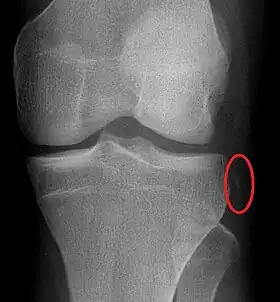

Enfin, Segond est un des plus éminents spécialistes du genou au XIXe siècle en France. Reprenant les expériences d’Amédée Bonnet (1820-1858), il publie en 1879 une étude sur « les épanchements sanguins du genou par entorse »[12]. Observant un traumatisme qui porte aujourd’hui son nom, la « fracture de Segond », qui se produit par arrachement du bord antéro-latéral du plateau tibial et s’accompagne généralement d’une rupture du ligament croisé antérieur, il en décrit les autres signes cliniques et, à cette occasion, il signale l'existence d'une « bande nacrée », oubliée depuis lors, redécouverte en 2012 au CHU de Brest[13] et en 2013 à l'hôpital universitaire de Louvain (nl)[14], et renommée par ses nouveaux auteurs « ligament antéro-latéral »[15].